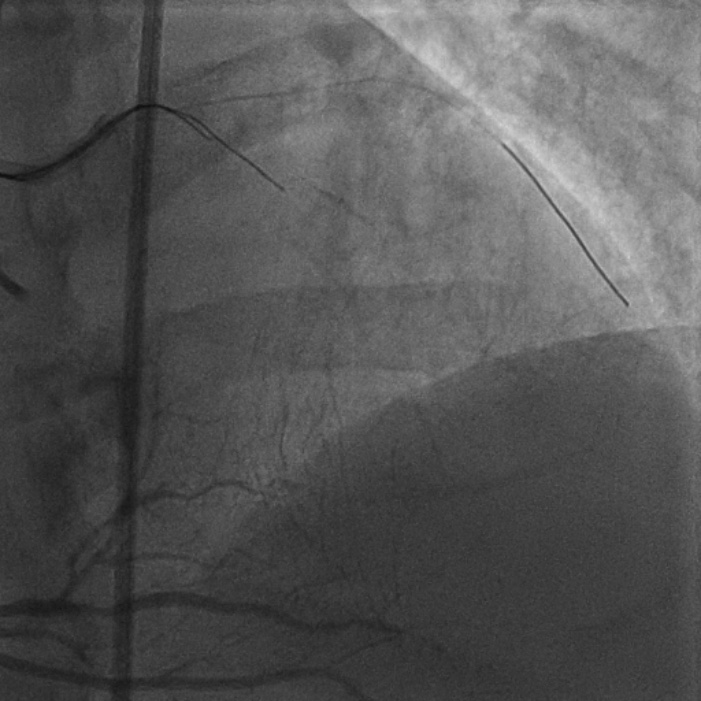

8F JL coronary guide catheter was taken from the right femoral artery and a TIG diagnostic catheter was taken from right radial artery and bilateral angiograms were taken. A floppy guide wire was placed in Lcx and ostial Lcx lesion was predicated with a 2*12 mm non compliant balloon. An IVUS catheter was placed over Lcx wire and under IVUS guidance a Gaia 3 coronary wire (Asahi, Japan) over a micro catheter was used to probe the ambiguous osmium of LAD (T1). Using contralateral injection in RCA, the Gaia 3 wire was seen extending into the false lumen in distal LAD. A Conquest Pro 12 (Asahi, Japan) was then taken over a micro catheter using a parallel wire strategy and successfully negotiated in distal true lumen of LAD (T2). After pre dilatation of LAD, Conquest Pro wire was exchanged for a floppy guide wire over a micro-catheter. IVUS run was then taken from LAD to LM and LCx to LM for vessel sizing. In view of the discrepancy in size of LAD/LCx and LM, 2 coronary stents were placed in a V technique from LM to LAD and LM to LCx and deployed. The stents were then post dilated and final kissing balloon inflation was done and the results were optimised by IVUS. Final cine showed well expanded LM LAD/LCx stents with TIMI 3 flow (T3).